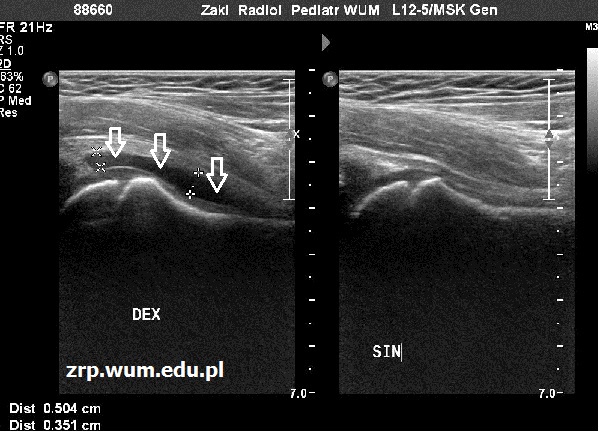

Przypadek 33: 5-letni pacjent zgłosił się do IP z powodu bólu prawego stawu biodrowego od kilku dni; w wywiadzie zapalenie ucha środkowego przed 2 tyg.

Rozpoznanie: W badaniu USG stwierdzono obecność płynu w prawym stawie biodrowym (strzałki) oraz prawidłowy obraz głowy kości udowej. Zwiewne zapalenie stawu biodrowego (Coxitis fugax).